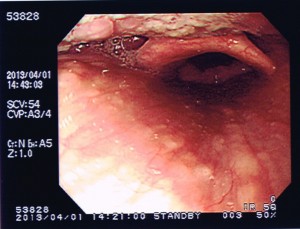

← 声帯

← 声帯

数年前、風邪をおして4ステージを歌ってひどく喉を潰したことがありました。ボイストレーナーによるとELTの持田香織さんが声を壊したときと同じ症状とのこと。ポリープがあるかも?と思っていましたが、写真のように大丈夫のようです。